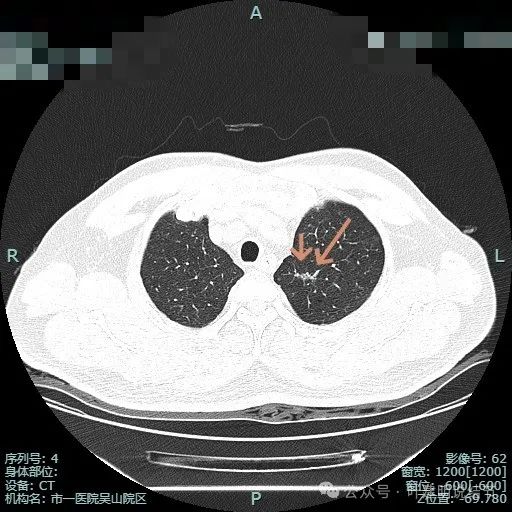

右中叶微小磨玻璃结节病灶E,轮廓清,密度甚低,风险极小。

左下叶少许斑片状影,轮廓欠清,少许慢性炎或伴纤维增生或肺泡上皮增生。